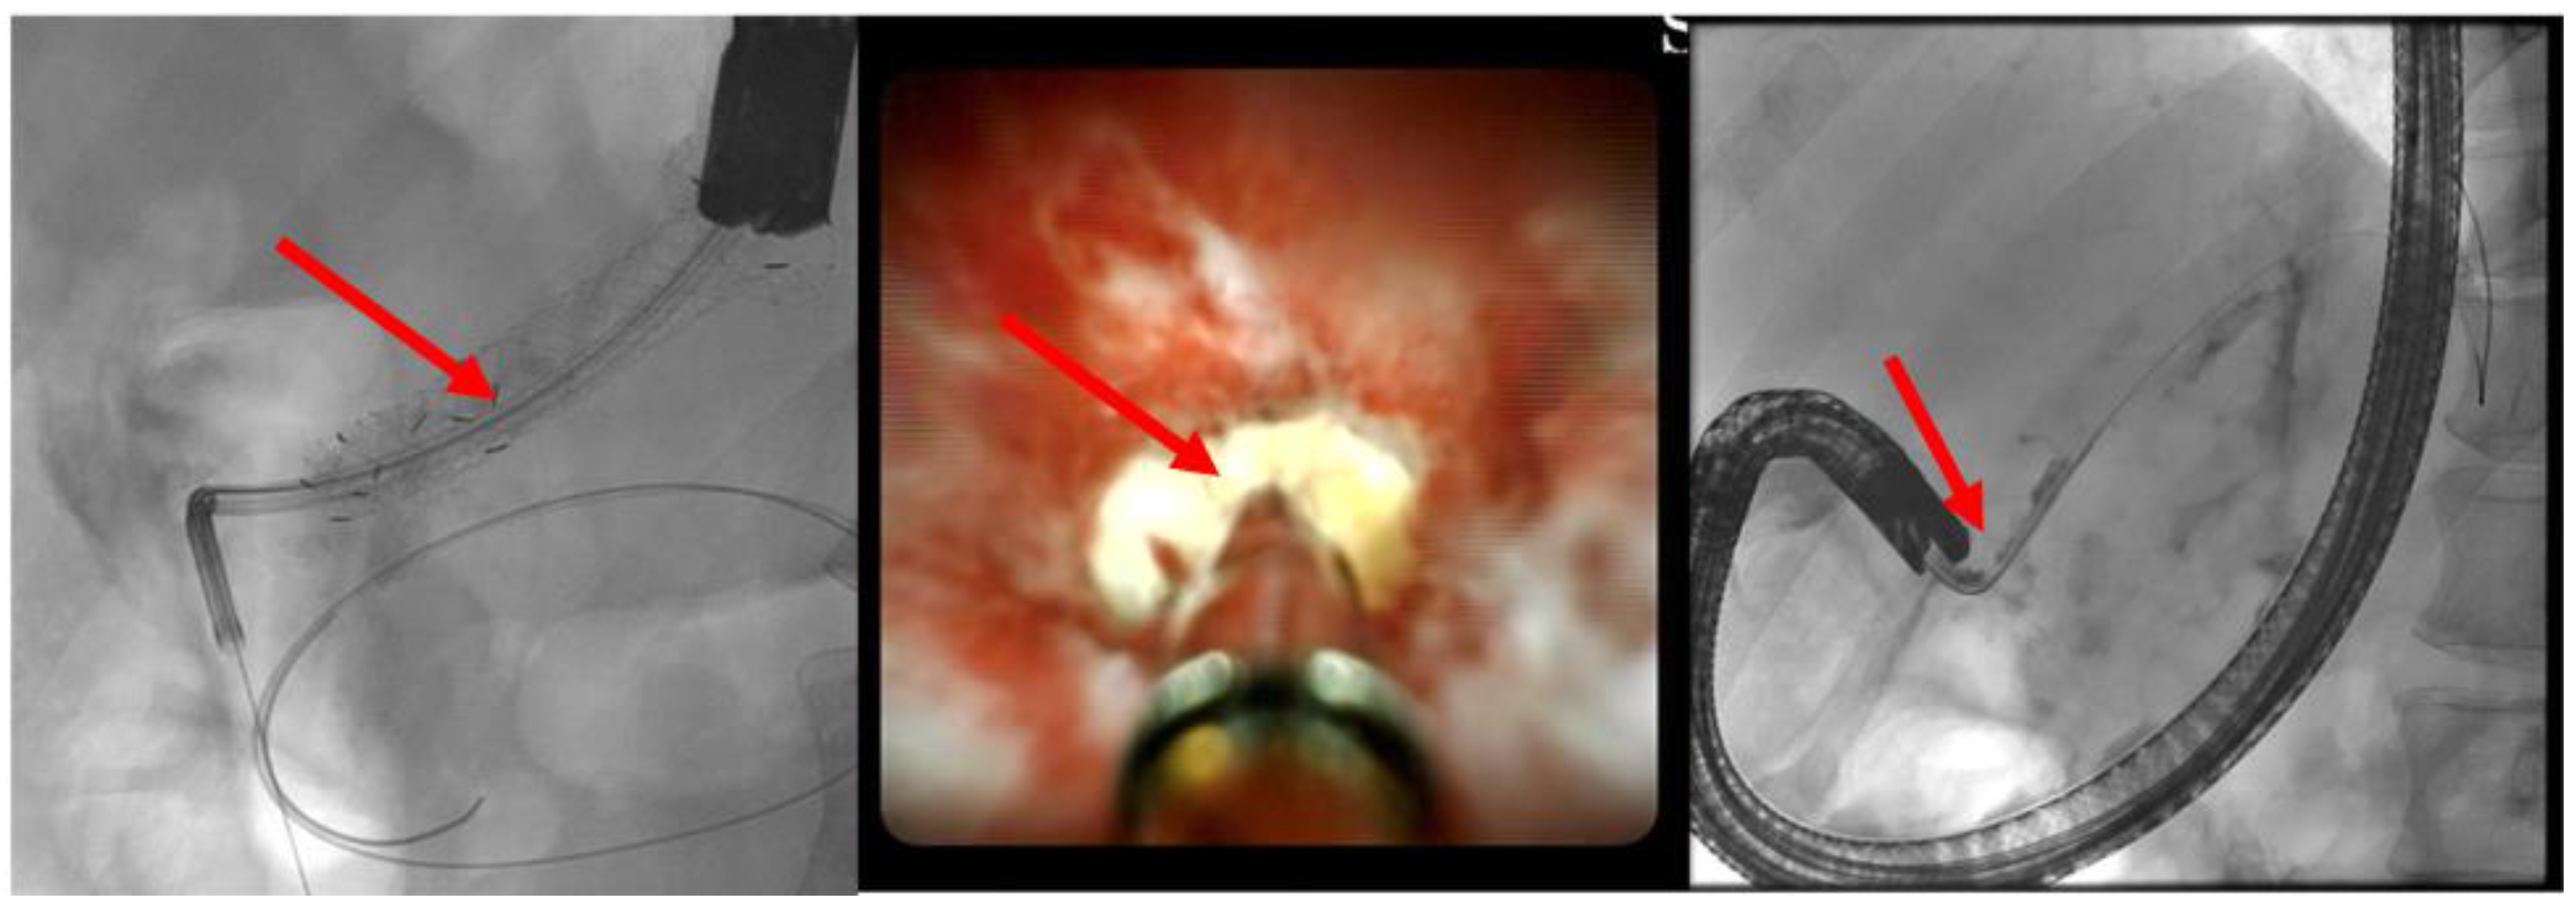

(A) EUS-ERP rendezvous technique: If the wire can be passed through the papilla and the papilla is accessible with the endoscope, a duodenoscope is employed. The guidewire is then grasped with forceps and pulled out, enabling subsequent conventional ERP with endoscopic papillary balloon dilation (EPBD) and stent placement (Figure 3 and Figure 4).

(B) EUS-guided pancreatic duct drainage (EUS-PD): If the wire cannot pass through the papilla or if the papilla is unreachable with a standard duodenoscope or enteroscope (e.g., post-gastrectomy, Roux-en-Y reconstruction, Kausch–Whipple surgery; see the above), the wire is advanced as far as possible into the pancreatic duct following an EUS puncture. An access site is then created along the wire using a Will HF ring knife (MTW Endoskopie Manufaktur W. Haag KG, Wesel, Germany) followed by dilatation of the typically transgastric access using a 6-mm bile duct dilatation balloon (Boston Scientific, Ratingen, Germany). The choice of prosthesis, which is inserted, depends on factors such as the site and width of the pancreatic duct system or the direction of the puncture. If a wide pancreatic duct is punctured near the obstruction, antegrade drainage (pancreaticogastrostomy/pancreaticoduodenectomy) can be attempted by using a self-expanding metal stent (SEM or LAMS, Boston Scientific, Ratingen, Germany) or a straight plastic Amsterdam prosthesis (Medi-Globe, Achenmühle, Germany) (Figure 5).

Figure 3. EUS puncture with a 19-G needle tangentially toward the papilla; the wire is passed out of the papilla via a ring knife, followed by device change of the duodenoscope.

Figure 4. After the device change, the wire is grasped with forceps and passed out, followed by a conventional ERP with stent placement (red arrow).

Figure 5. Dilated pancreatic duct (red arrow) in history of necrotizing pancreatitis—suspected DPTS; EUS-guided pancreatography (left panel) with following insertion of a plastic prosthesis (red arrow) for retrograde drainage (middle panel) and endoluminal (endoscopic) control of the right plastic prosthesis position (red arrow—right panel); selected from the clinical picture library of the reporting Dept. of Gastroenterology, Hepatology and General Internal Medicine.